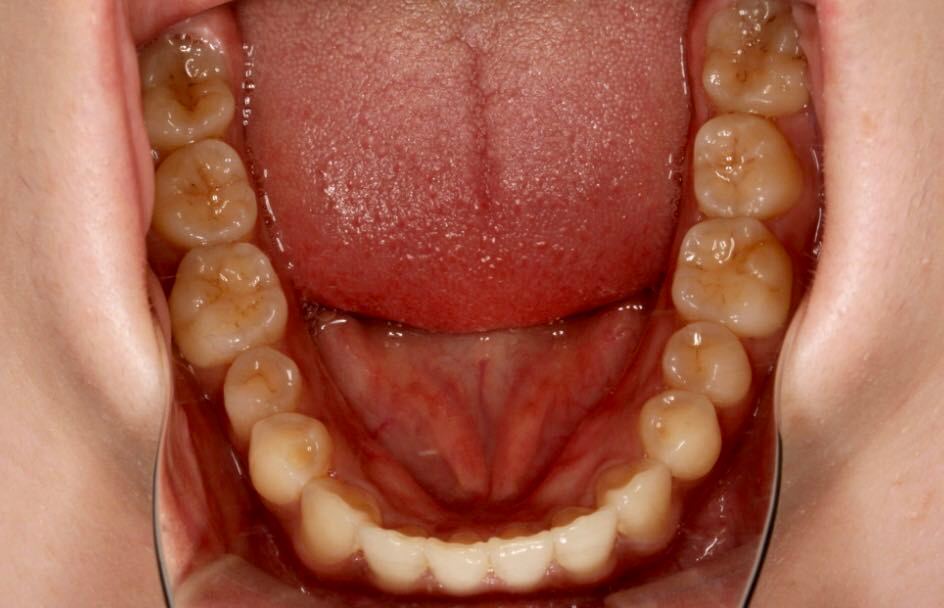

矫正前口内照:

口内:恒牙列,牙列拥挤(中度)。上下颌牙弓呈方圆型。左右对称。右侧磨牙近中性关系,左侧磨牙近中关系,右侧尖牙远中关系,左侧尖牙远牙中性关系。上颌中线偏右2mm,下中性居中。

矫正后口内照:

目前阶段:全口牙齿排列整齐,中线居中。前牙覆合覆盖正常,尖磨牙关系达I类咬合关系。总疗程约18个月。